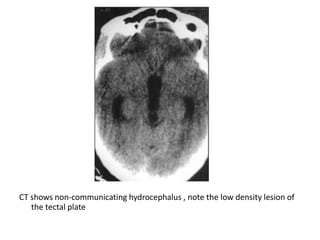

CT shows non-communicating hydrocephalus , note the low density lesion of

the tectal plate

-CT :

-Typical CT finding is homogenous expansion of

tectal plate, isodense to grey matter with

minimal enhancement in postcontrast image